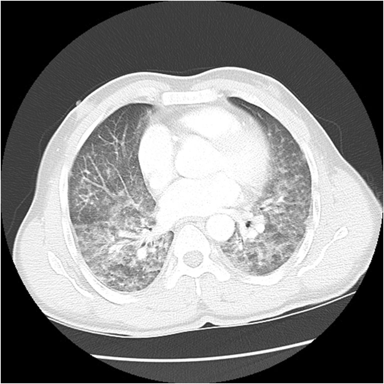

CT主要表现为三处非常细小的渗出(图1-3箭头所示):

图1

回到这个小护士病例,根据水痘表现,加上影像学表现为GGO、小结节周围GGO,应该比较符合的,可以临床诊断为水痘肺炎。但本病例仅发现3个小病灶,没有广泛累及,推测原因可能是先前可能接种过水痘疫苗,肺部累及较轻。

本例患者是因筛查新冠CT检查而意外发现的轻微的水痘肺炎,病程中并无明显咳嗽、气急与呼吸困难。当然此例水痘肺炎是建立在临床诊断基础之上,有必要进一步跟踪随访。